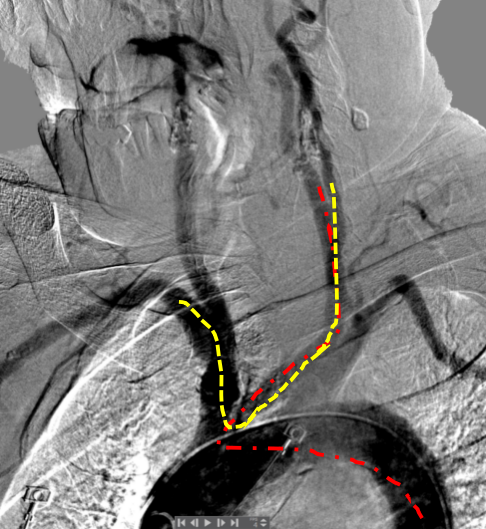

多数情况下,经桡并不是CAS的优选通路,但对于某些特殊情况下,经桡确实更好,例如牛角弓和主动脉弓先天闭锁。高老师在2020年的一期宣武CRC星期五详细讨论过这个问题,推荐感兴趣的同道点击阅读别无他途:当颈动脉支架遇到主动脉闭锁,左桡入路来帮忙!。对于这个患者,经右桡做,导引导管的“拐角”似乎差不多(图6)。

图6. 经桡入路(黄色)和经股入路(红色)的路径比较。